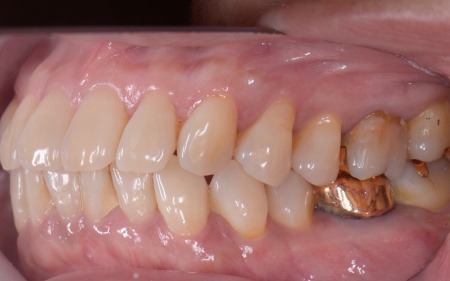

| 相談内容 | 「左右の奥歯がグラグラしていて、固いものが噛みにくい」とご相談いただきました。 |

| カウンセリング | 拝見したところ、上下左右の奥歯計8本(第1大臼歯、第2大臼歯)に重度の歯周病が認められました。 歯周病は歯を支えている骨や歯ぐきに炎症が起こる病気です。進行すると歯がぐらついたり、噛む力が弱くなったりします。 さらに悪化すると歯を失う可能性が高くなるだけでなく、周囲の歯にも影響が広がることがあります。 特に下の奥歯2本(左右第1大臼歯)は歯を支えている骨が著しく減少して歯が大きく揺れており、治療して温存することは難しい状態でした。 また、左上の奥歯(第1大臼歯)は過去に詰め物で治療されていましたが、その下で虫歯が再発しています。 以上のことから、下左右の第1大臼歯は抜歯後に歯を補う治療、その他奥歯の治療、再発した虫歯の治療が必要と診断しました。 |